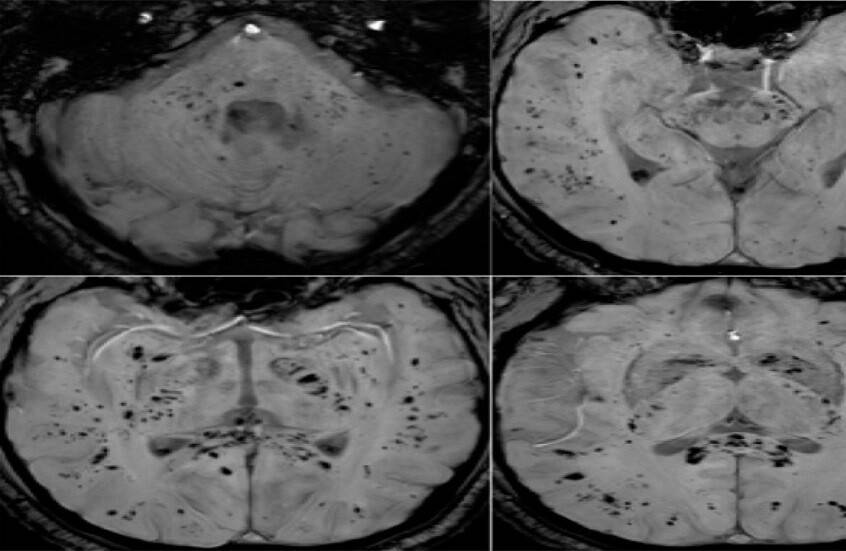

أظهر تحليل صور بالرنين المغناطيسي أن فيروس كوفيد-19 يترك أثرا لا يُمحى في الدماغ، ويستمر تأثيره حتى بعد التعافي التام.

أظهرت دراسة حديثة أجراها علماء في جامعة غريفيث الأسترالية ونُشرت في مجلة Brain, Behavior, & Immunity Health أن فيروس كوفيد-19 لا يؤثر على الجهاز التنفسي فحسب، بل يترك أثرا ملموسا على الدماغ، ويستمر تأثيره حتى لدى الأشخاص الذين يعتبرون أنفسهم متعافين تماما، حتى إذا لم تظهر عليهم أعراض واضحة.

وأوضح الباحث الرئيسي الدكتور كيران تاباليا أن الفريق استخدم طرق التصوير بالرنين المغناطيسي متعددة الوسائط لدراسة المادة الرمادية والبيضاء في الدماغ، وهي مهمة للذاكرة والوظائف الإدراكية والصحة العامة للدماغ. ووجد الباحثون اختلافات ملحوظة في أنسجة الدماغ وموادها الكيميائية العصبية وشدة الإشارة وبنية الأنسجة لدى المتعافين من كوفيد-19، حتى في حالات الإصابة التي اعتبرت بسيطة.

وأضاف تاباليا: "تبين أن التغيرات في أنسجة الدماغ مرتبطة بشدة الأعراض"، ما قد يفسر مشكلات إدراكية طويلة الأمد مثل تدهور الذاكرة والتركيز، والتي قد تستمر لشهور أو حتى سنوات بعد الإصابة.